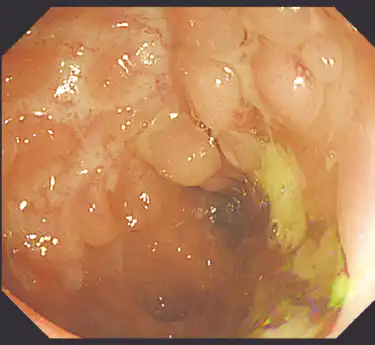

治療前 -

小腸・大腸を中心にとびとびに潰瘍を作る病気です。口の中(口内炎)、食道、胃、十二指腸、肛門と消化に関わる多くの臓器に病気を作る可能性があります。潰瘍性大腸炎と同じく再燃と寛解を繰り返す病気とされますが、時間とともに病状が進行・悪化することが多く、進行することで生じた腸の狭さ(狭窄)や腸の穴(穿孔・瘻孔)を内科治療で完全に修復することは困難で、外科との連携も重要となります。

治療後 -

小腸の症状が中心の人は、軽い症状のまま長い時間が経過することで診断が遅れ、発見された時点ですでに外科手術が必要になる患者さんもいます。